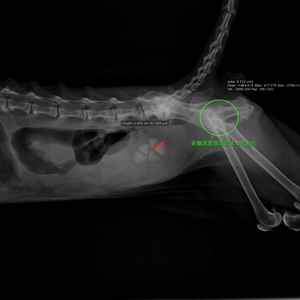

インフォメーション 3ページ目 2025/03/07 4月の日曜予約診察のお知らせ 2025/03/04 膝蓋骨内方脱臼 2025/02/27 3月の日曜休診のお知らせ 2025/02/19 春の健康診断始まります 2025/02/14 耳道内腫瘤による閉塞性慢性外耳炎 2025/01/17 電話のお掛け間違いにご注意ください! 2025/01/14 診療費の価格改定について 2024/12/30 年末年始のご案内 2024/12/17 来年の日曜診療の変更および受付時間の変更について(※重要です!) 2024/12/12 腹腔鏡による潜在精巣摘出 <<前のページへ|1|2|3|4|5|6|7|8|9|10|次のページへ>>